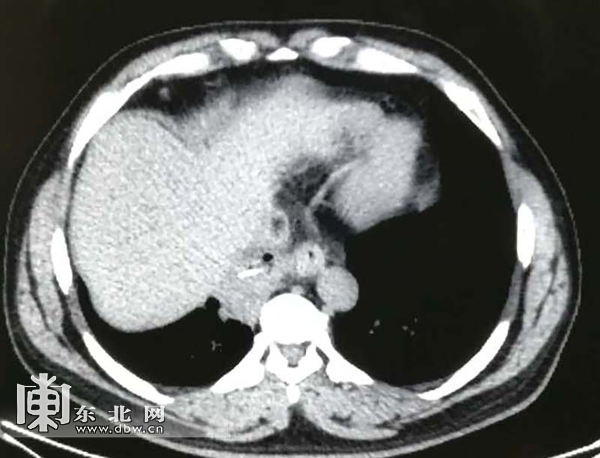

剧烈的咳嗽伴有大量异味的脓痰让他整夜无法入睡,严重影响了他的生活。最后尹先生在家属的陪同下慕名来到了哈医大肿瘤医院胸外科,经多名专家联合会诊后仍考虑为胸腔异物引起的肺感染。结合反复详细的问诊以及患者的回忆,胸腔的异物考虑为鱼刺的可能性大。鱼刺随着食管的蠕动以及食物的挤压作用下,刺穿了食管,扎入了肺脏,引起了周围的炎症。随着时间的推移,这根危险的鱼刺还可能会在胸腔内继续游走,万一扎破胸腔内的大血管,那将危及到生命。因此,最后决定由胸外科主任徐世东教授带领的医疗团队为尹先生进行急诊手术,解决潜在的隐患。

4个月的时间使鱼刺周围形成了非常致密的粘连,术中胸腔内组织结构因炎症水肿也变得很紊乱,这极大地增加了手术的难度。经过5个多小时的仔细解剖游离,发现鱼刺已经完全刺入了肺内,在切除了一个肺叶后,终于取出了长近3厘米的鱼刺,手术很成功,术后,尹先生发热咳嗽症状立刻缓解。当他见到从自己肺内取出的鱼刺时,说自己以后再也不吃带刺的鱼了。